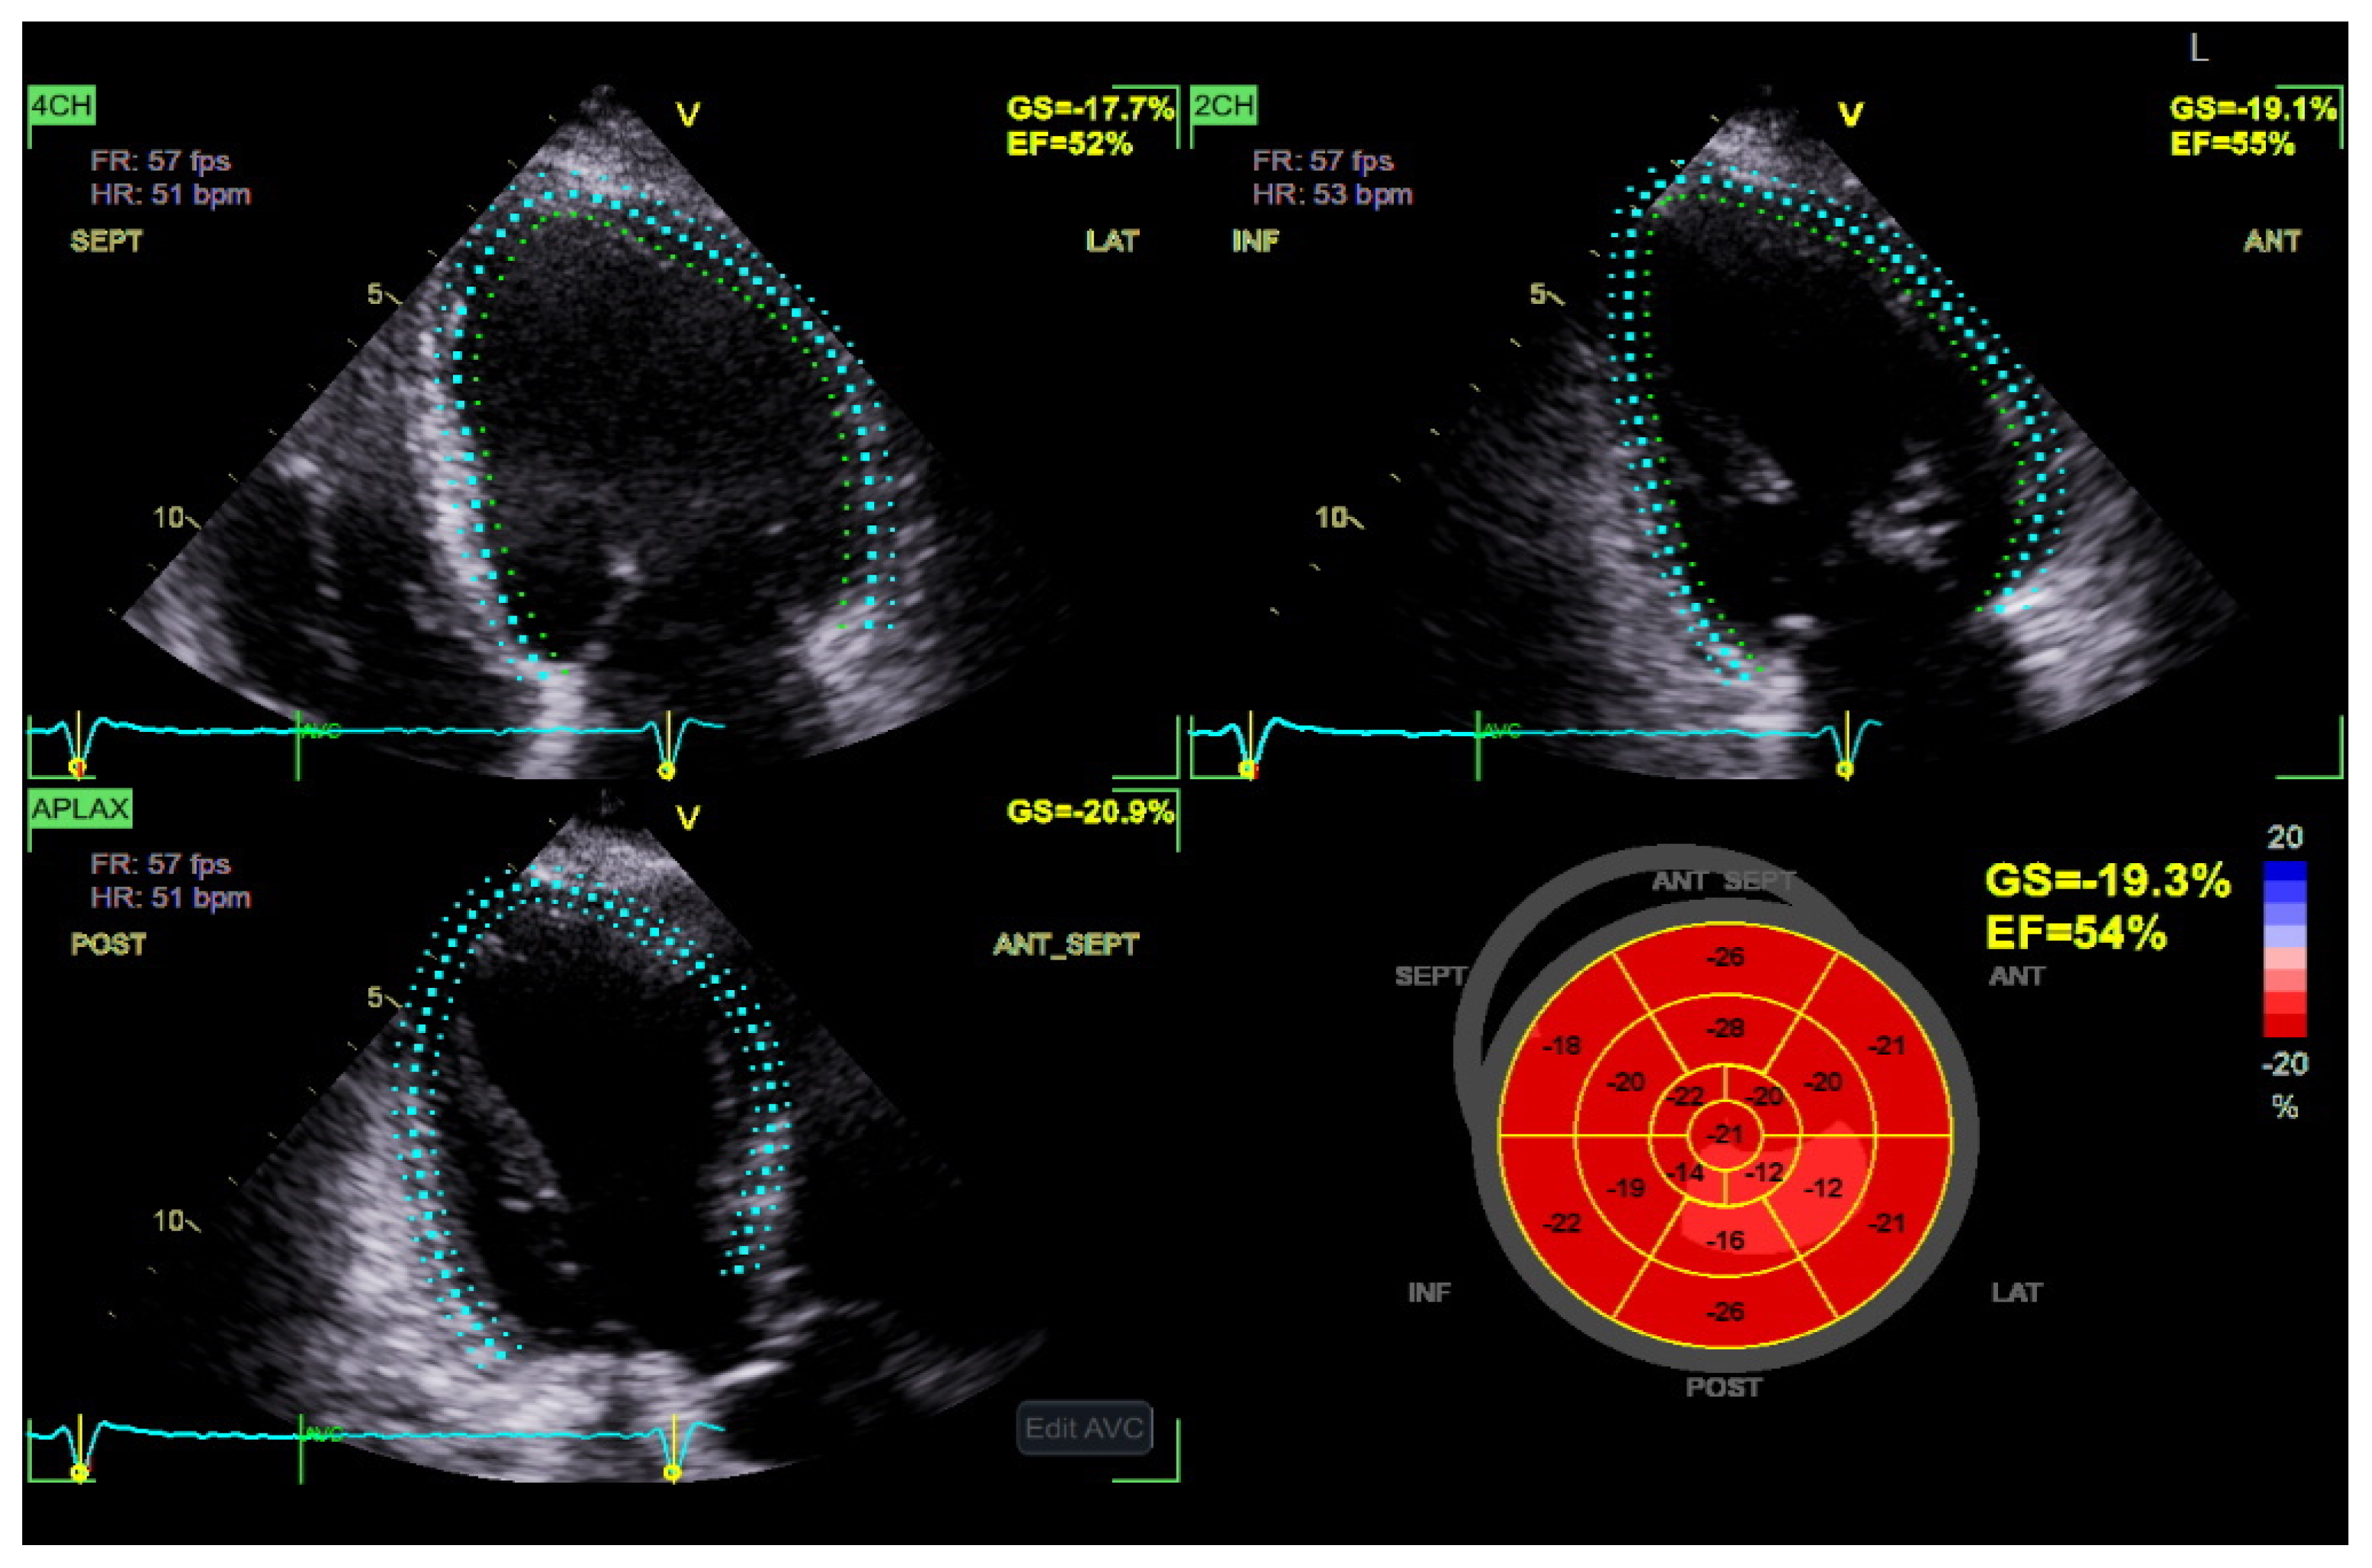

4.1. Speckle Tracking Echocardiography of the LV

| Speckle Tracking LV | GLS, GCS, GRS, segmental strain parameters | -Requires good image quality -GLS declines before GCS/GRS; segmental variations may confound interpretation; superior sensitivity than LVEF | -GLS is a stronger predictor of CV mortality than LVEF in diabetic patients -Optimization of DM treatment and reduction in HbA1C may improve GLS |